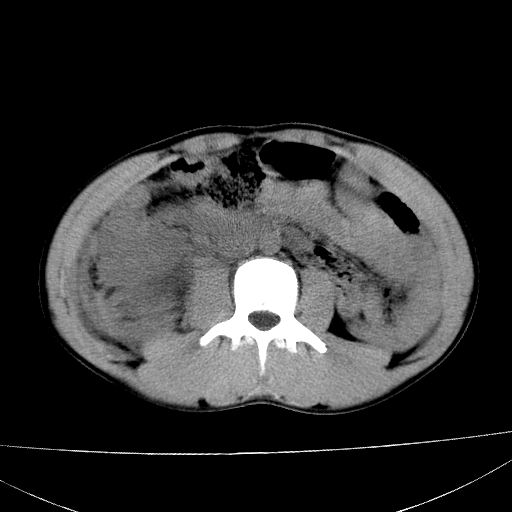

标题: CT15860:男,21岁,腹部外伤2小时伴胸疼。 [打印本页]

标题: CT15860:男,21岁,腹部外伤2小时伴胸疼。

肝脏及肾脏明显有损伤性改变并激发腹腔内积液(血),以肝脏撕裂及肾周积血显著。

1)肝破裂伴腹腔积液(血)。2)右肾破裂伴右肾包膜下及肾周血肿。3)腹部空腔脏器穿孔可能。4)右侧少量胸腔积液(血)。

肝肾挫裂伤,右肾周及包膜下血肿,腹腔积液,不排除空腔脏器穿孔,建议行增强检查

肝肾挫裂伤,右肾周及包膜下血肿,腹腔积液